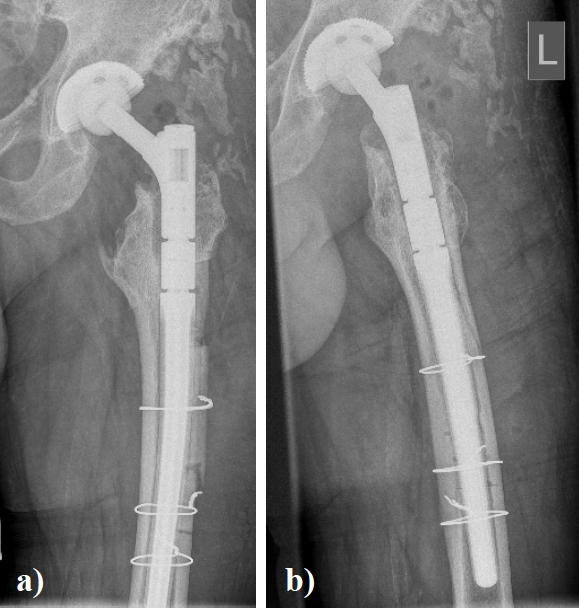

In August 2013 THA was performed due to a girdlestone situation after septic osteoarthritis of the hip (Figure 1) in a 46 year old male patient using a MRP Titan revision stem (Diameter: 18mm, length: 140 mm) (Peter Brehm GmbH, Weisendorf, Germany) and a cementless cup (Allofit - IT; Diameter 54 mm, Zimmer, Warsaw, USA) and a ceramic on ceramic bearing (head diameter: 36 mm) (Figure 2). The patient was 175 cm tall and weighed 105 kg (body mass index: 34.3 Kg/ m2). 2 weeks later revision surgery due to recurrent dislocation (Figure 3) was performed. Revision of the acetabular component was done using an Allofit - Classic- cup, Diameter 56 mm (Zimmer, Warsaw, USA)). The neck component was exchanged from small to medium size (Figure 4). A ceramic on PE bearing was implanted (head diameter: 32 mm). Postoperative healing was uneventful. The patient was out of any complaints. In February 2016 the patient started suffering from slight thigh pain but detected crepitation in the region of the left hip. X-ray of the left hip in 2 planes in May 2016 revealed an asymmetrically gap of the stem / neck junction (Figure 5). During revision surgery of the left hip breakage of the cone of the morse taper junction was visible (Figure 6). Removal of the well-fixed stem was performed via a distal fenestration. After fixation with cerclage wires a bended MRP Titan revision stem (Diameter: 19 mm, Length: 200mm with long neck and extension sleeve) was implanted using a 32 mm ceramic head (Figure 7). Postoperative healing was uneventful.

Figure 2. X - ray of the left hip in 2 planes: ap view a. and lateral; b. view shows THA using a MRP Titan revision stem with a short neck and a cementless cup.

Figure 4. X - ray of the left hip in 2 planes: ap view a. and lateral; b view shows status after revision of THA using a long varus neck and a cementless cup.